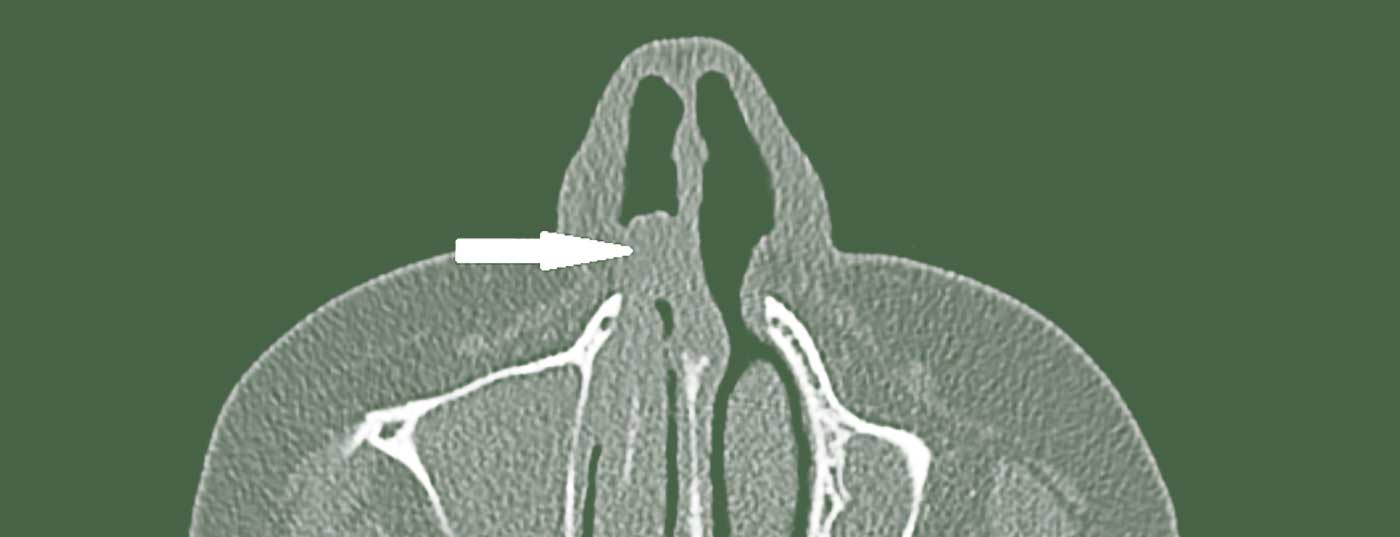

Das primäre Schleimhautmelanom im Kopf- und Halsbereich ist selten. Es verhält sich jedoch im Vergleich zum kutanen malignen Melanom deutlich aggressiver. Entsprechende Leitsymptome sollten Anlass sein für eine rasche HNO-fachärztliche Abklärung.